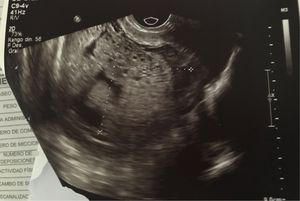

Mola hidatiforme

Paciente de 24 años en ecografía imagen en panel de abeja, bhcg 300000